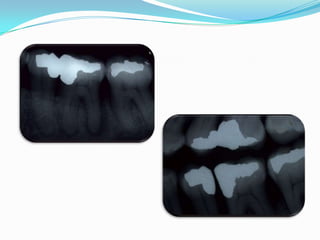

Secuencia de Tratamiento

Instrumentación    Técnica     Conometría

Tercio Apical   Escalonada

Rx

Rx Final

Compactación

Al ras, indica esta pasada   Ajuste a 1 mm

Secuencia de Tratamiento Desgaste Acceso Tercio Conductometría Compensatorio Cervical

Secuencia de Tratamiento Instrumentación Técnica Conometría Tercio Apical Escalonada

Secuencia de Tratamiento Rx Rx Final Compactación

Al ras, indicaesta pasada Ajuste a 1 mm